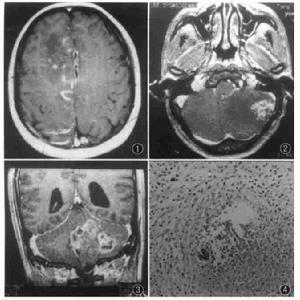

肉眼所見大腦充血水種,並有廣泛的神經細胞變性,腦組織多處有出血灶。顯微鏡檢查見神經細胞變性壞死血管周圍有淋巴細胞、單核細胞和多形核白細胞浸潤形成“血管周圍套”有的膠質細胞增生和多形核白細胞堆積形成結節。病灶主要見於大腦基底節,腦幹灰質和白質也可侵犯小腦和脊髓。